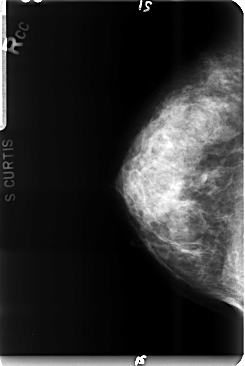

B_3495_1.RIGHT_CC

RIGHT_CC LINES 4752 PIXELS_PER_LINE 3184 BITS_PER_PIXEL 12 RESOLUTION 50 NON_OVERLAY